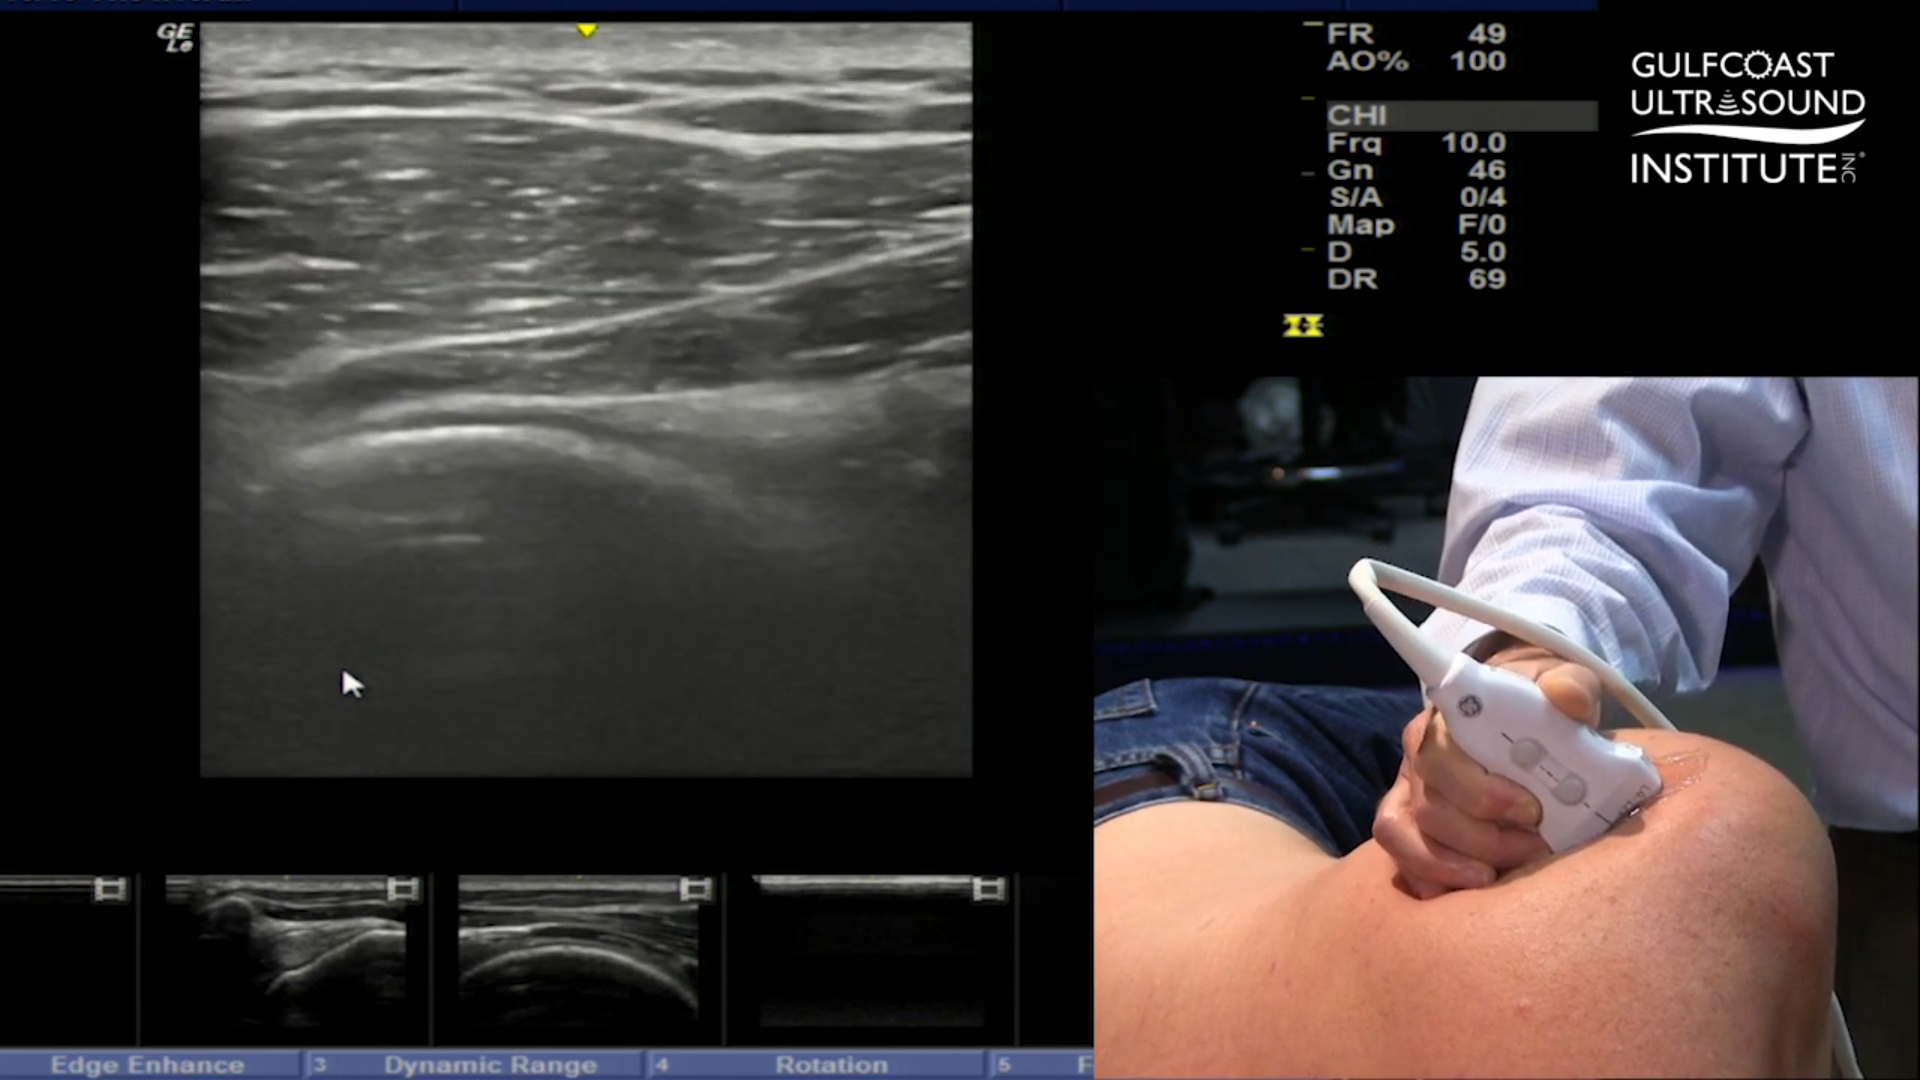

When scanning the posterior aspect of the glenohumeral joint in short axis, the key structures to identify are the humeral head, the glenoid, and the labrum. But in practice, many clinicians find themselves running into the same obstacle: the rounded convexity of the humeral head tends to rise above the glenoid, creating a barrier to both visualization and needle placement. This can make an otherwise straightforward injection feel unnecessarily complicated.

So how do you get around the problem? The solution is surprisingly simple. Instead of fighting the anatomy, you reposition your view. Imagine the humeral head as the sun on the horizon. By applying pressure to the posterior portion of your transducer, the “toe”, you tilt the probe in such a way that the humeral head effectively “sets.” This slight angulation shifts the convexity out of the way, opening up a clear trajectory for your injection from lateral to medial.

By tilting the probe to “set the sun,” you’re not changing the anatomy; you’re simply changing your angle of visualization. This small tweak eliminates the humeral head’s obstruction and provides a more favorable view of the posterior glenohumeral joint. The improved alignment makes the needle path more straightforward, reduces frustration, and enhances accuracy. For clinicians, it’s a reminder that sometimes the best solutions come down to understanding your tools and making smart adjustments.